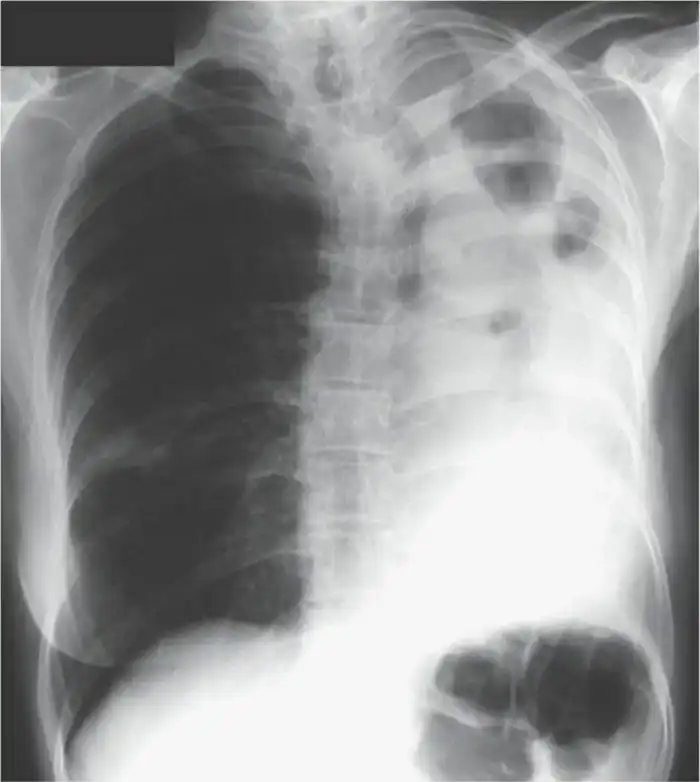

Рентгенограмма большой грибковой опухоли:

Бэтси в итоге спасли, и она успешно перешла от острой формы к хронической, оставшись на этом свете с кашлем, необходимостью постоянного лечения и жутковатым жизненным опытом. В её случае врачи пришли к мнению, что виновником заболевания стала компостная куча на заднем дворе, где у Бэтси был сад. Но так ли всё просто?

“Аспергиллез” лишь общее название весьма нескромной группы болезней, вызываемых грибами рода Aspergillus. В большинстве своем, заболевание наиболее характерно для уже больных или сильно ослабленных людей. Это все, кто перенес или всё ещё болеет самыми разными болезнями, связанными с легкими: от туберкулеза и хронической обструктивной болезни легких до астмы и тяжелых форм аллергий. В случае с Бэтси она обзавелась аспергилломой, проще говоря, в её легких разросся грибной мицелий. Чтобы в бронхе или в легком выросли грибы, недостаточно просто вдохнуть споры плесени. Вы и так это делаете постоянно. Для того, чтобы они прижились, необходимо иметь повреждения (в виде гранулемы, например). И тогда, попав в полость гранулемы, абсцесса или кисты, споры прорастают, и начинает расти аспергиллома.

Процесс может быть очень долгим, ткани бронхов и легких будут постепенно разрушаться, вовлекаясь в формирование детрит - мертвых клеток в основе гриба. Больной может долгое время просто покашливать, пока его состояние постепенно деградирует, приступы становятся сильней, появляется слизь и мокрота, она становится зеленоватой, присоединяются хлопья, кровь, куски бронхов и гриба. Сама по себе аспергиллома может вырасти практически где угодно, но на первом месте легкие из-за наибольшего количества спор, попадающих туда, на втором ушной канал. Но если споры попали в лишенный защиты организм, унести их может и в печень, и в почки. Где при низком или нарушенном иммунитете - обязательно что нибудь вырастет. Жаку вот не повезло с верхнечелюстной пазухой.